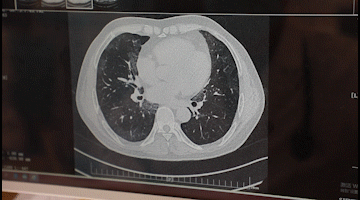

李先生入院后,胸科醫(yī)院吳昌歸院長、朱運奎副院長組織科室進行了深入討論,為其做了詳細檢查。醫(yī)生先做了導航下氣管鏡冰凍活檢,但病理未獲明確診斷。根據(jù)胸部CT特征、病變過程治療的反應,醫(yī)生懷疑是罕見的肺泡蛋白沉積癥。再經肺泡灌洗液分析、PAS染色及診斷性分段灌洗后復查,證明醫(yī)生診斷正確。李先生確診為“肺泡蛋白沉積癥(繼發(fā)性)、肺炎、1型呼吸衰竭,并伴有慢性乙肝、高血脂癥等。

經過4次的治療,李先生沉著于肺泡內蛋白樣物質漸漸消失,灌洗液為透明色。復查胸部CT肺部病變明顯吸收。經再次灌洗治療后病變完全吸收,恢復健康。